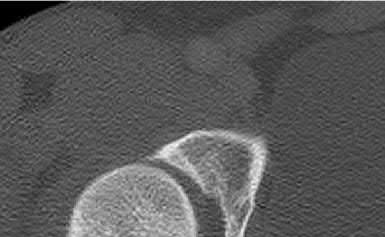

A 12-year-old obese boy presents with vague left thigh and knee pain. He is diagnosed with a Slipped Capital Femoral Epiphysis (SCFE) as seen in similar clinical scenarios.

During percutaneous in-situ fixation, unrecognized penetration of the guide wire into the hip joint occurs. What is the most likely specific complication resulting from this technical error?

Chondrolysis is a severe complication of SCFE characterized by rapid destruction of the articular cartilage. While it can occur idiopathically, its most established iatrogenic cause is unrecognized intra-articular hardware penetration. The 'approach-withdraw' fluoroscopic technique is required during pinning to assure pins are entirely intraosseous. Avascular necrosis (AVN) is usually due to damage to the epiphyseal blood supply (retinacular vessels) secondary to the initial displacement, forceful closed reduction, or posterosuperior pin placement.